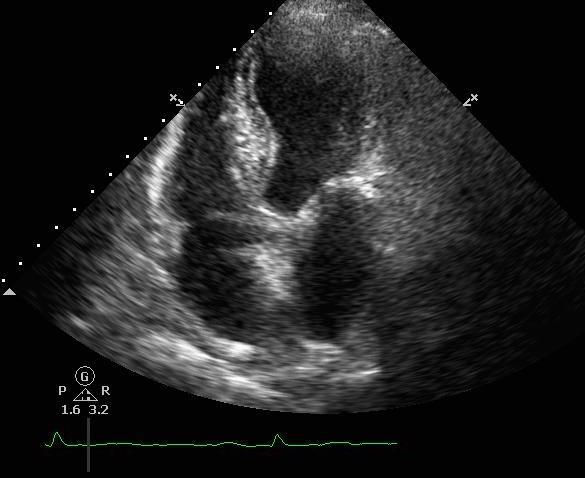

ECG showed sinus rhythm. 24hours ECG ( Holter ) showed ectopics < 1% , pause < 2secs [not significant].Echo showed EF 45-50% with hypokinesia (as shown above) – no thrombus or severe aortic stenosis. Creatinine was ~130umol/L ( not markedly raised).Ad hoc Coronary Angiography was performed:LM <30% stenosesLAD Prox 70-80%LCx ISR (Prox-Mid) 80-90%RCA ISR (Pros) 80% , DominantPCI to LCx ISR – DEB 2.75/20mm , PCI to LAD (ostium-mid) – DES 2.75/33mm + 3.5/13mm